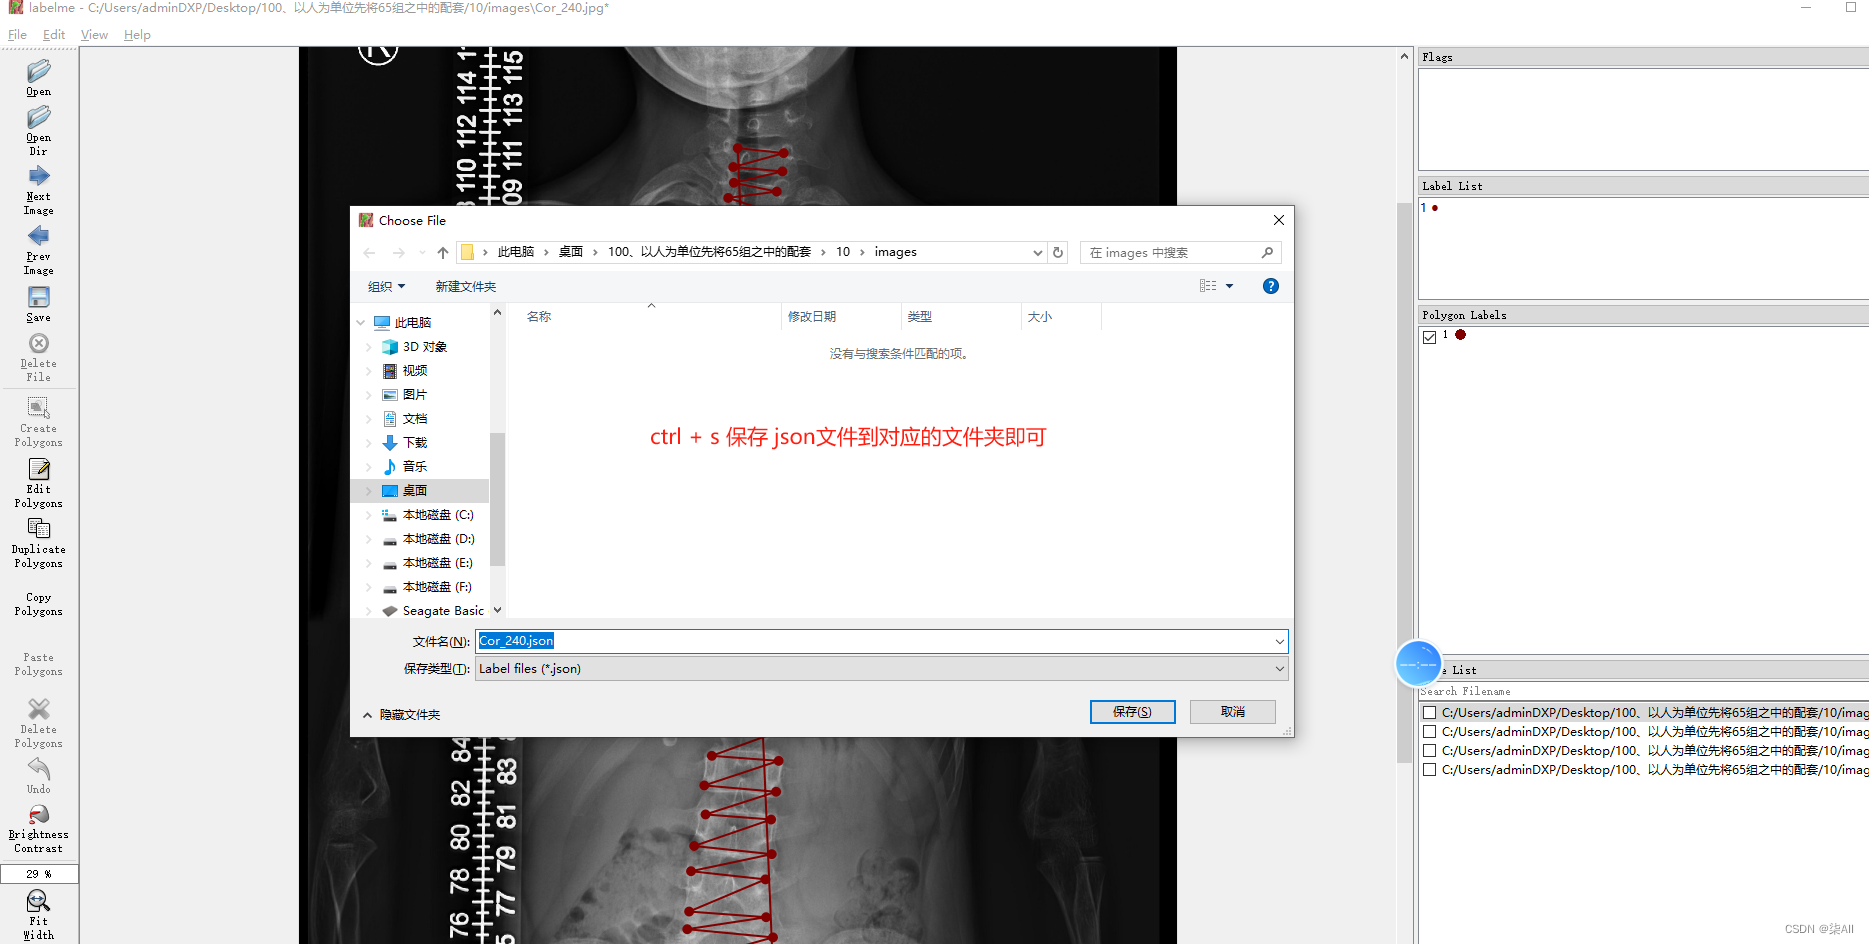

2、开始标注(以冠状位为例,其他方位是一样的操作,视频教程)

冠状位关键点标注教程

3、冠状位标注结果

4、标注过程注意事项